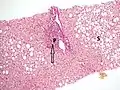

Once the biopsy is obtained, a pathologist will study the sample. Cirrhosis is defined by its features on microscopy: (1) the presence of regenerating nodules of hepatocytes and (2) the presence of fibrosis, or the deposition of connective tissue between these nodules. The pattern of fibrosis seen can depend on the underlying insult that led to cirrhosis. Fibrosis can also proliferate even if the underlying process that caused it has resolved or ceased. The fibrosis in cirrhosis can lead to destruction of other normal tissues in the liver: including the sinusoids, the space of Disse, and other vascular structures, which leads to altered resistance to blood flow in the liver, and portal hypertension.[82]

Trichrome stain, showing cirrhosis as a nodular texture surrounded by fibrosis (wherein collagen is stained blue).